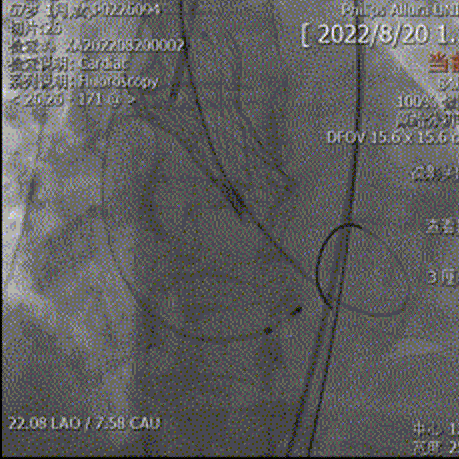

主动脉根部造影可见钙化影,采用18mm球囊预扩,有轻微腰征,无造影剂渗漏,左冠显影正常。

主动脉根部造影

球囊预扩